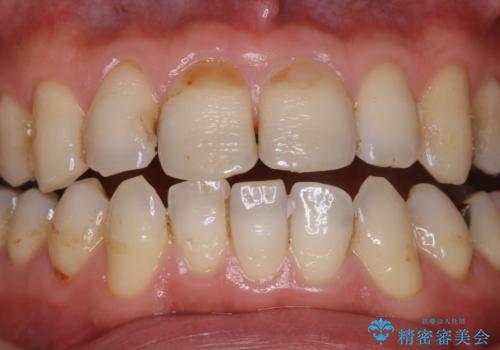

歯の表面に、茶色く色が残っている所がありますが、これは詰め物の変色の所と、虫歯になっている所です。以前に、CR(コンポジットレジン)による虫歯治療がされています。

CRは経年的劣化や、着色してしまうことがあります。PMTCでクリーニングを行うと、古いCRが目立つことがあるため、気になる際は詰め替えを行います。

茶色くなっている部分が、着色なのか、劣化なのか、虫歯によるものなのかは判別が難しいことがあります。そのため、定期的にPMTCを行うことで状態の確認が的確に行えます。

また、治療が開始される前などにも、全体的にクリーニングを行いご自身本来の歯の色、状態を精密に確認することが大切です。